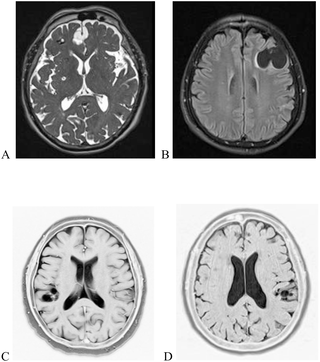

Subarachnoid neurocysticercosis in a rural area of the Bolivian Chaco: A population-based survey through the use of a novel urine antigen assay

Author summary Human neurocysticercosis (NCC) is a parasitic disease caused by the localization of the larval stage of Taenia solium in the central nervous system after ingestion of the parasitic eggs. It represents a relevant health issue in low-middle-incom…